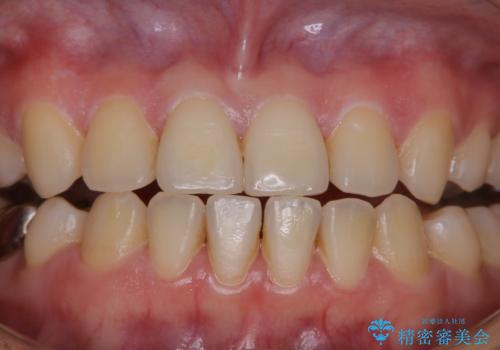

治療の前にPMTCできれいでツルツルな歯に

- 今後治療を進めていく予定で、まずはきれいにクリーニンングから行いたいとのことでした。PMTC60分コースを行いました。